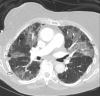

Figure 2

Figure 2. Contrast CT scan chest.

Arrows showing patchy areas of ground glass opacity